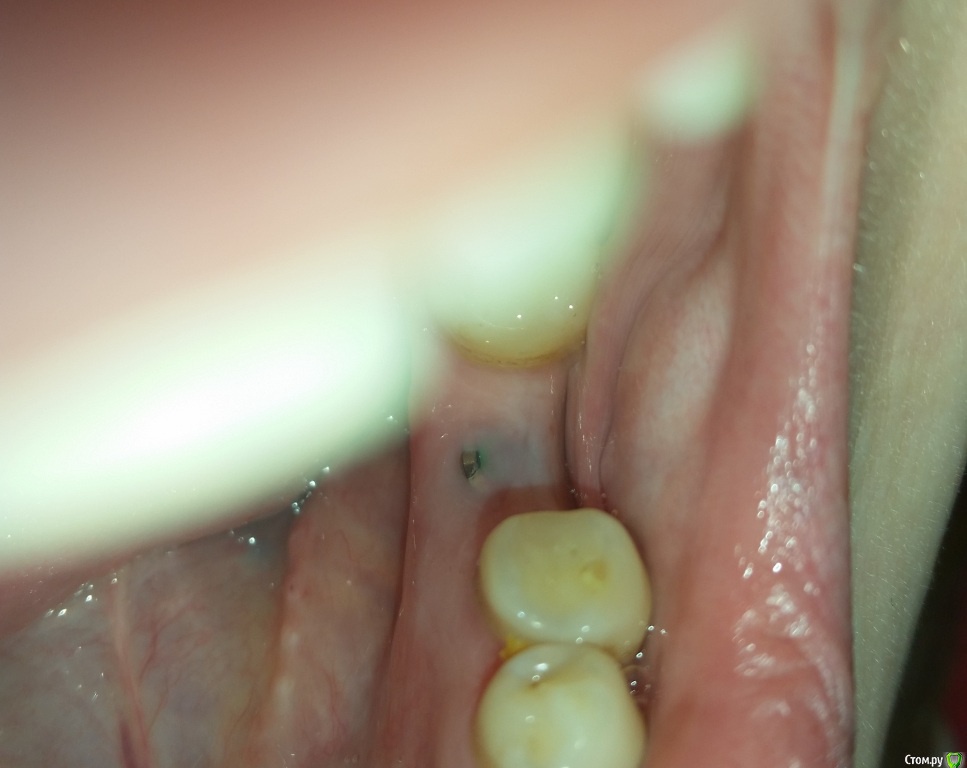

Валерия2020 Опубликовано 3 декабря, 2016 Поделиться Опубликовано 3 декабря, 2016 Прошла неделя после снятия швов. Десна до конца не срослась, виднеется зеленая заглушка.Переживаю что это ворота для инфекции. Постоянно пользуюсь хлоргексидином, холисалом, солкосерил дентальный. Хорошо прополаскиваю - и после этого края десны будто раздвигаются и заглушка видна еще больше. Что мне делать в такой ситуации? Как уберечь себя от воспаления? И можно ли в таком состоянии доходить 3 месяца до установки формирователя. Спасибо. (на фото десна после ночи с солкосерилом, к вечеру она сильнее расходится) Ссылка на комментарий

Валерия2020 Опубликовано 4 декабря, 2016 Автор Поделиться Опубликовано 4 декабря, 2016 убыль кости у шейки, обнажение витков.Десна не срослась с имплантом установленным с правой стороны. Ссылка на комментарий